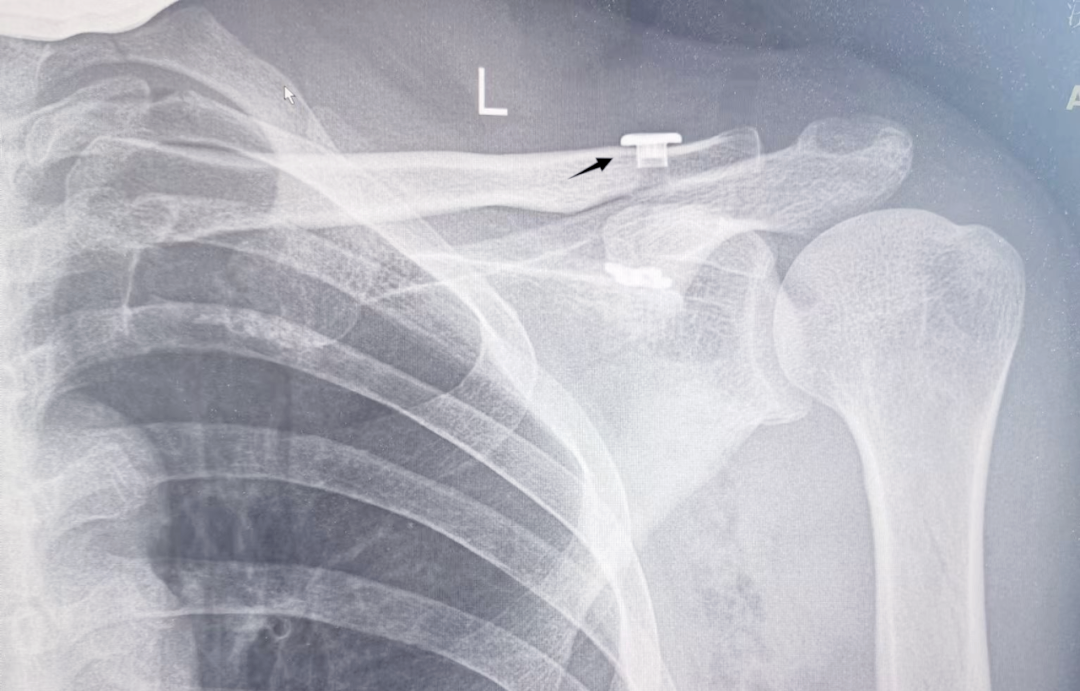

众所周知,骨科患者身上植入的钢板,往往需要二次手术进行取出。然而,现在有一种新的技术,使得这种钢板无需取出也成为可能。近日,章丘区人民医院骨创伤科成功应用带袢钛板内固定技术,为患者治疗肩锁关节脱位,这一技术让患者避免了取钢板的痛苦。

近日,区人民医院骨创伤科运用精湛的微创技术,在臂丛麻醉下,为一位肩锁关节脱位患者实施了小切口肩锁关节低切迹带袢钛板系统内固定术,手术顺利完成。该技术不仅创伤小、手术时间短,而且术后恢复迅速,更令人欣喜的是,患者无需经历二次手术的痛苦,大大减轻了患者的身心负担。“真的非常感谢你们,这个手术简直太棒了,再也不用担心挨第二刀了。” 47岁的郑女士在出院时,由衷地对骨创伤科主任王亮和主治医师韩峰表达了感激之情。

在肩锁关节脱位的治疗上,传统的方法是采用锁骨钩钢板固定,但这种方法需要在肩峰下放置锁骨钩钢板的远端,其尖钩可能会压迫到冈上肌腱和肩峰下滑囊,引发多种并发症,并且需要二次手术取出内固定。而章丘区人民医院骨创伤科则采用了小切口肩锁关节低切迹带袢钛板系统内固定术来治疗肩锁关节脱位,这种技术无需二次手术取出内固定,从而避免了二次创伤。